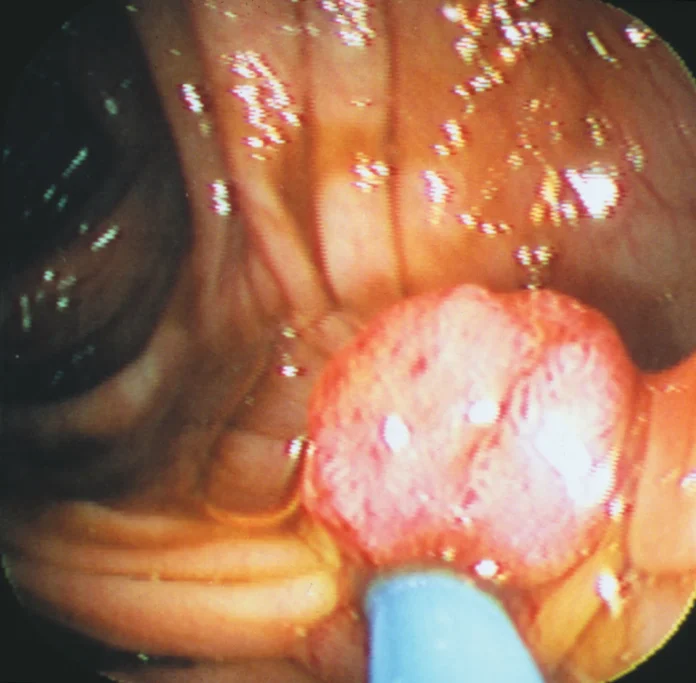

- Surgery: This is often used to remove a tumour if it’s localized and hasn’t spread to other body parts.